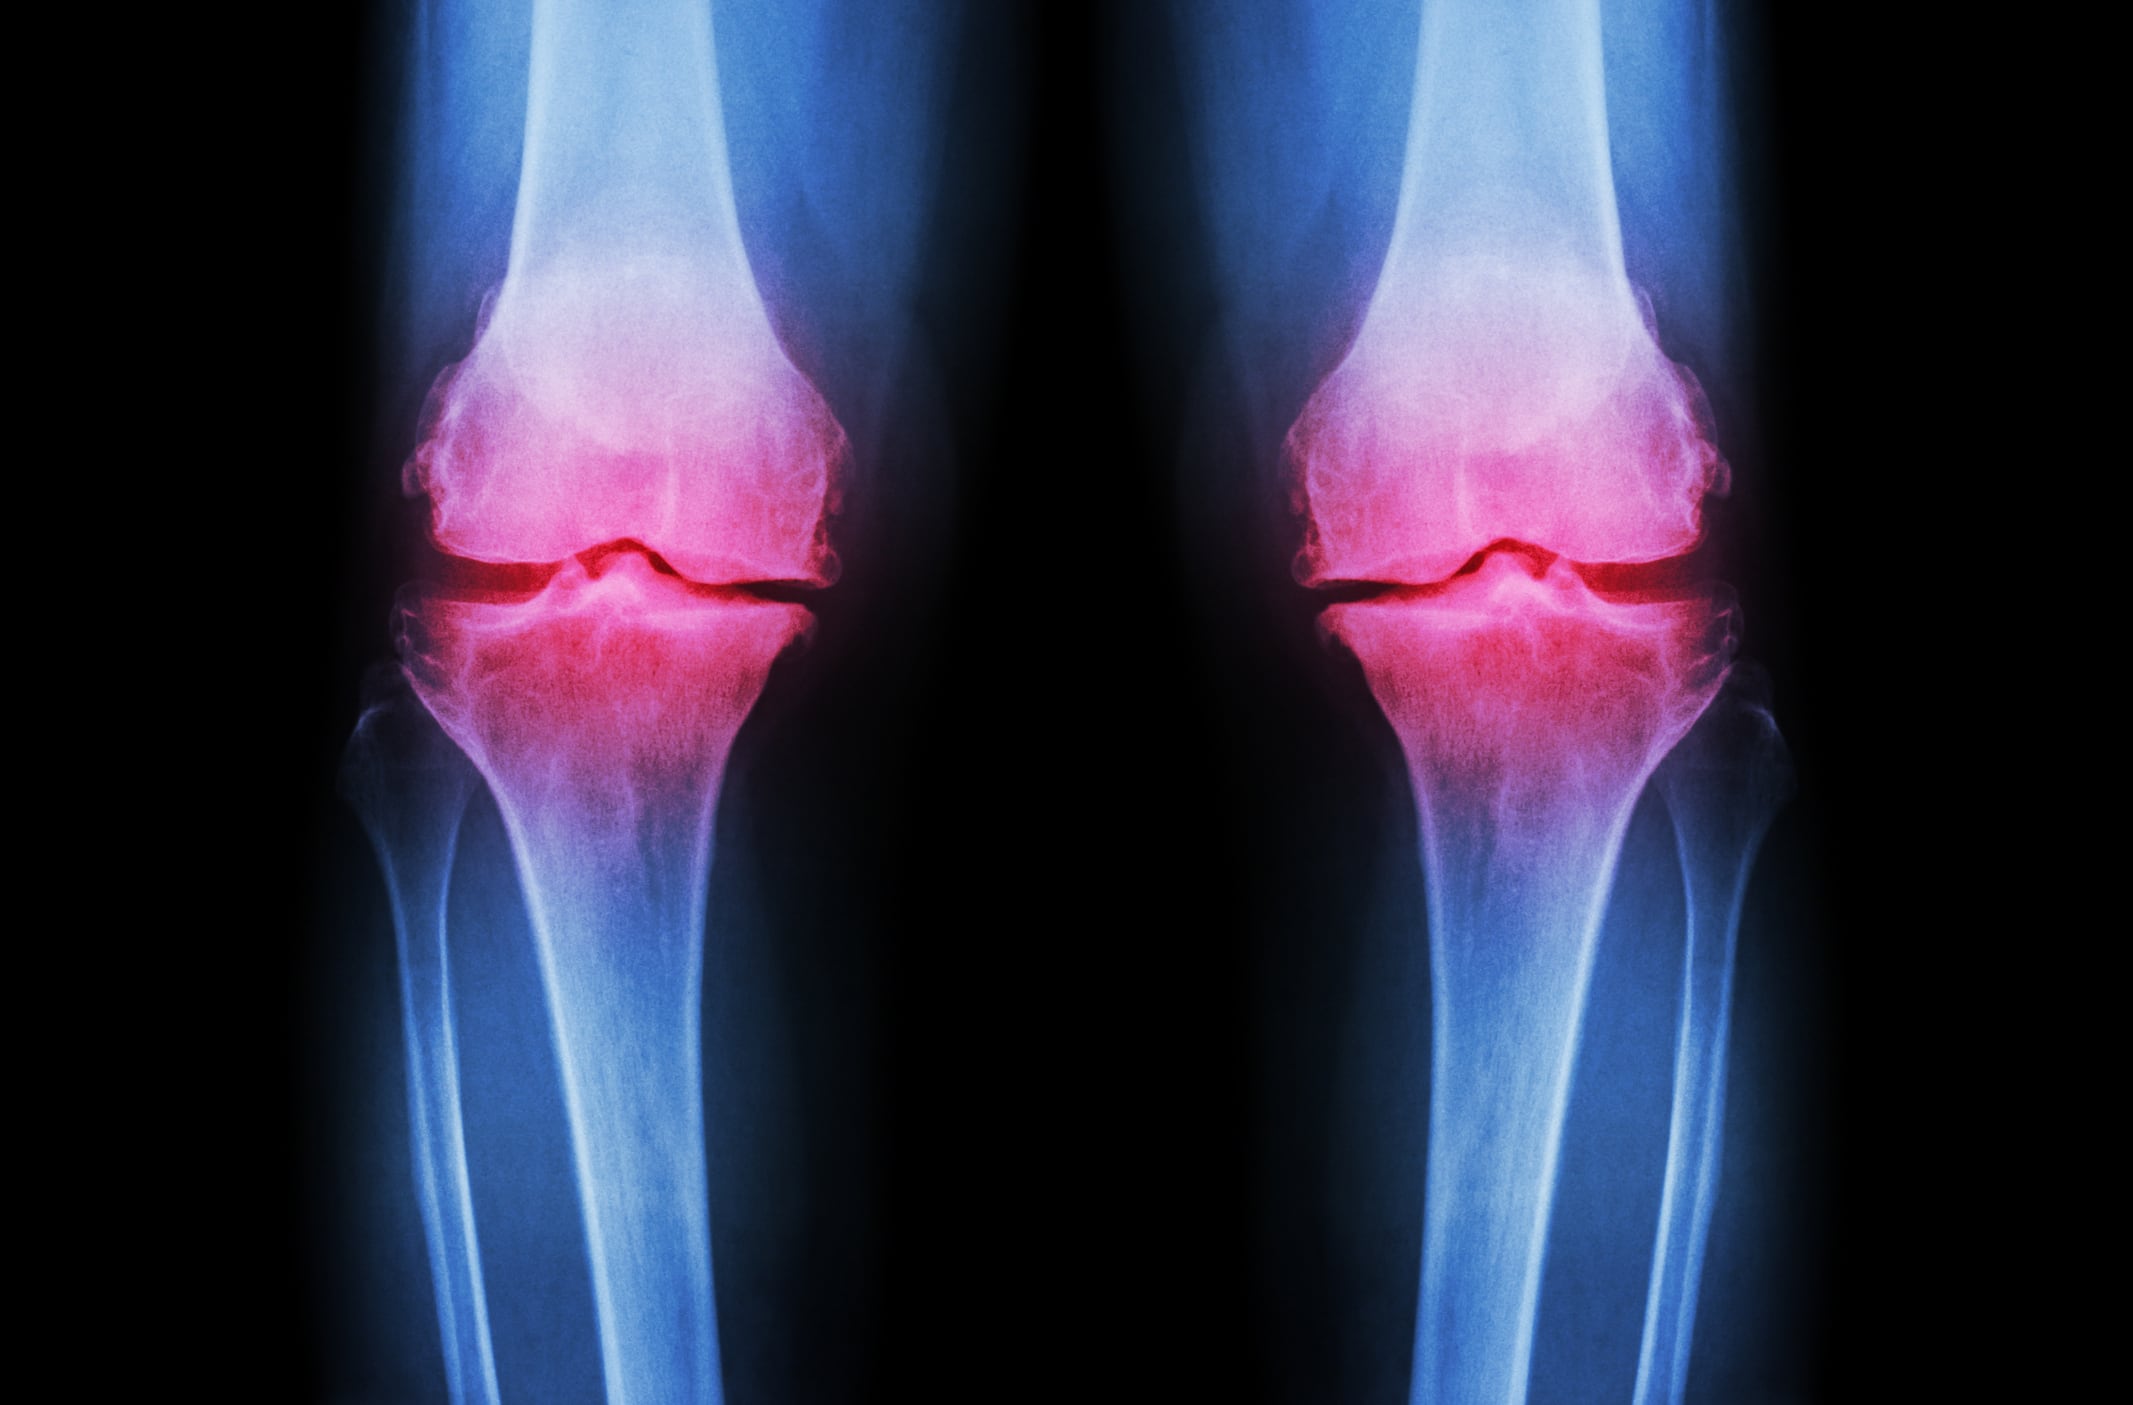

Osteoarthritis (OA) affects millions of people worldwide and according to The World Health Organization Global Burden of Disease Study 2010, hip and knee OA is the 11th leading cause of disability. The number of people affected with symptomatic OA is only expected to increase due to the aging population and the obesity epidemic.

The independent, randomized double-blind, placebo-controlled trial evaluating the efficacy of the ingredient supplier’s flagship ingredient, NEM brand eggshell membrane, was published in the Journal of Arthritis. At eight different university medical centers, 166 subjects diagnosed with grade 2 or grade 3 osteoarthritis of the knee were studied.